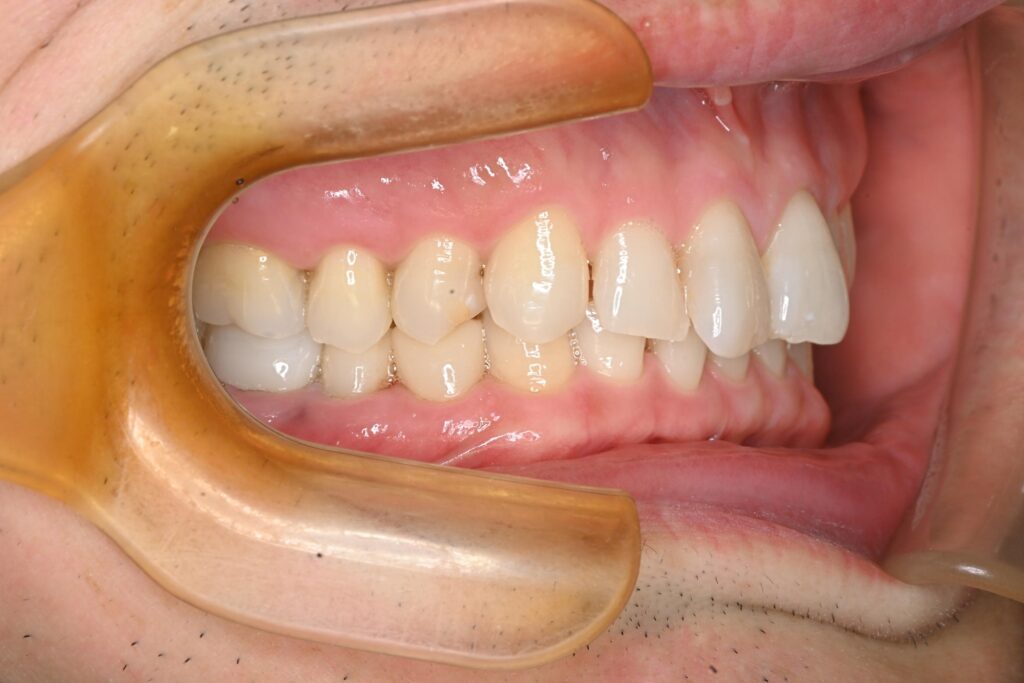

治療結果

After